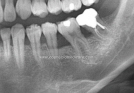

Clinical Cases

• Case1

• Case2

• Case3

• Case4

• Case5

• Case6

• Case7

• Case8

• Case9

• Case10